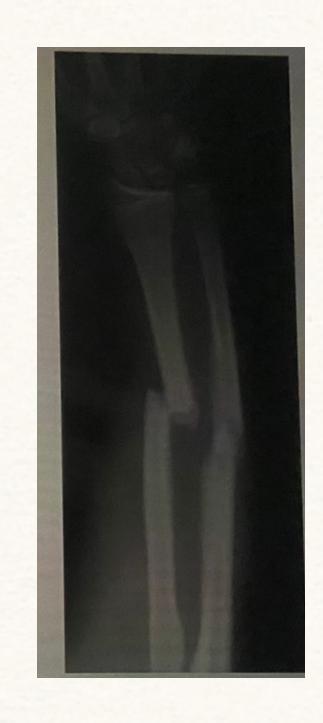

Galeazzi Fracture

-

Treatment: Surgery -

Monteggia Fracture

- Location: Proximal ulna fracture w/ radial head dislocation ย fracture of the proximal (or midโshaft) ulna with dislocation of the radial head at the elbow. ย

Q15: 35-year-old male with fracture - Treatment

35 years old male with this fracture, how would you treat it:

- Open reduction and internal fixation of ulna - Closed reduction of head of radius +/- fixation